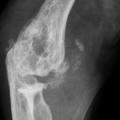

Les radiographies permettent de déceler des modifications ostéocartilagineuses asymétriques (mains, pieds, poignets, coudes, genoux), secondaires à la réaction inflammatoire autour des tophus, comportant :

• des érosions osseuses initiales caractéristiques : encoche épiphysaire (fig. 3) avec un éperon osseux (aspect en hallebarde) ;

• un interligne longtemps conservé (contrairement aux autres rhumatismes destructeurs) [fig. 3] jusqu’au stade de goutte chronique et l’absence de raréfaction osseuse périarticulaire permettant de différencier la goutte d’autres arthropathies ; à un stade avancé, la goutte tophacée peut avoir un potentiel destructeur à la fois articulaire et osseux (fig. 4).